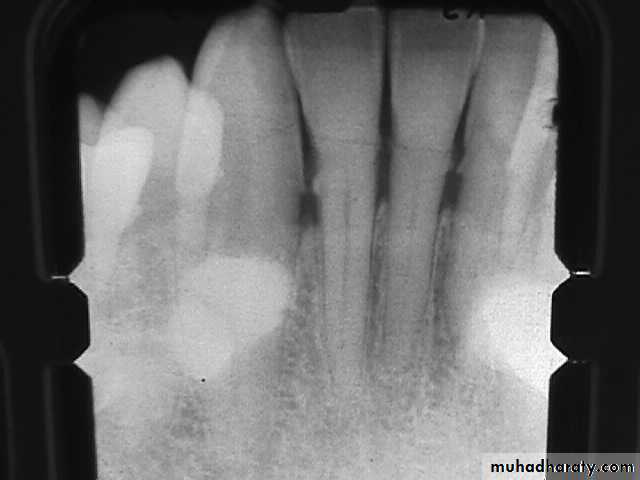

Teeth are composed of pulp (arrow on the secondmolar), enamel (arrow on the first molar), dentin (arrow onthe second premolar), and cementum (usually not visibleradiographically).